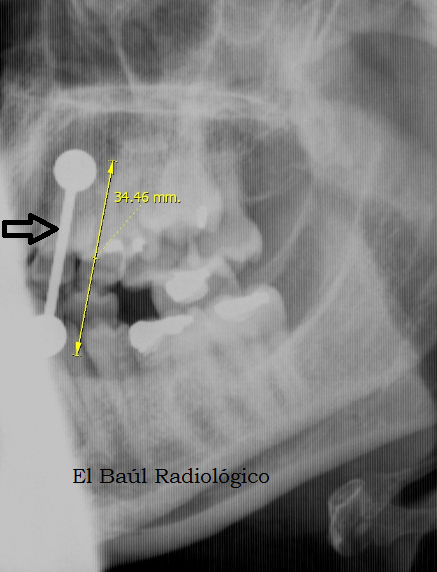

El Baúl Radiológico: "PIERCINGS" Y RESONANCIA MAGNÉTICA and MRI) by luis mazas Septiembre 2012.